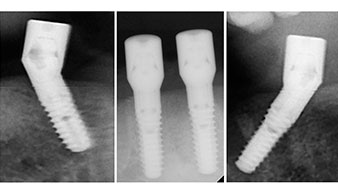

Un CT Scan à faisceaux coniques tridimensionnel (CBCT, Planmeca) a été réalisé au préalable afin de réduire les risques. Il a révélé une qualité et une quantité d'os disponible suffisante pour l'intervention chirurgicale et la restauration immédiate par la méthode All-on-four. En suivant le protocole de ce concept, les implants sont insérés au niveau de 35, 32, 42 et 45 en inclinant les implants distaux jusqu'à 45°, le profil d'émergence se déplace ainsi vers l'arrière et produit un polygone de stabilisation plus large (Fig. 3).

Le protocole chirurgical préconisé pour les implants utilisés (SKY, Bredent Medical) précise une vitesse de rotation de 1.200 tr./min. pour le pré-forage (Fig. 7 - 9).

Ceci correspond à la position suivante prédéfinie dans l'Implantmed. Nous voyons ici le contre-angle W&H tenu à un angle de 45° par rapport à la crête dans la région de 45 afin de préserver le nerf mentonnier. Le trou mentonnier sert de repére anatomique à tous les forages de cette région. Les forages suivants ont été effectués à la vitesse réduite de 300 tr./min. (Fig. 10 et 11).

Le prochain réglage programmé est destiné à la mise en place des implants. Dans notre cabinet, nous appliquons généralement un couple de 32 Ncm pour cette phase (Fig. 12 et 13).

Une grande stabilité primaire est une exigence essentielle à la restauration immédiate. Pour s'en assurer, le forage n'a pas été taraudé ici. L'unit de chirurgie Implantmed W&H utilisé ici est doté d'un mode spécial adapté qui peut être directement sélectionné et est indispensable à de nombreuses indications. Lors du positionnement des implants, les derniers tours ont été effectués avec une valeur supérieure à 32 Ncm et ont été effectués à la clef à cliquet. Dans un tel cas, nous recommandons d'utiliser la fonction d'auto -taraudage de l'implant et de tourner plusieurs fois les implants vers l'arrière et vers l'avant.

Ceci permet à l'implant de s'approcher de la position finale progressivement sans exercer de pression excessive sur l'os (Fig. 14).

Implants

Fig. 14